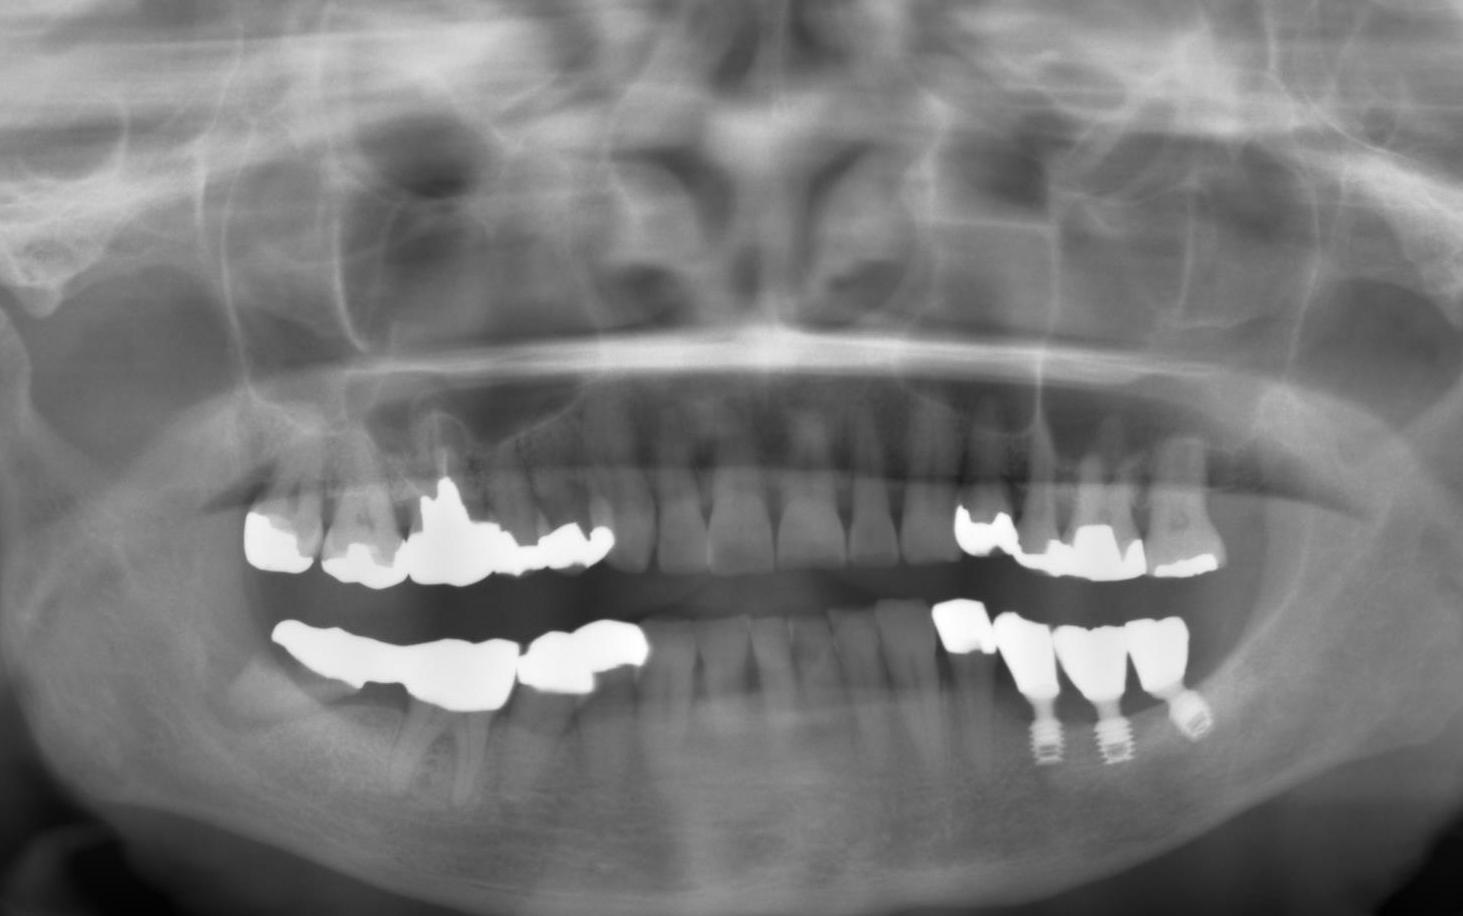

2、インプラント1次手術、2次手術

CT診断と3D画像に基づき

バイコンインプラントのショートタイプ(幅4ミリ、長さ5ミリ)の

インプラント埋入後3か月間は

インプラントが被せ物を入れて

噛む力に耐えられるだけしっかり顎の骨と

結合するのを待ちます。

3、被せ物の装着、メンテナンス

数回の試適を行い被せ物の大きさや

高さなどの確認を取り

患者様と一緒に色合わせ(シェードテイキング)を行い

歯の色を決定していきます。

続いて

ジルコニアを材料に使いCAD/CAMで

被せ物を作成します。